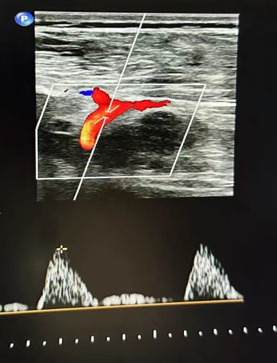

心功能室的李月医生在检查时敏锐捕捉到异常信号:双侧股总动脉血流频谱呈特征性“小慢波”——这通常是大血管严重狭窄的强烈提示。

然而,蹊跷之处随之浮现。医生仔细扫查了患者从股动脉直至腹主动脉的整条下肢供血通路,血管结构清晰,未见明显狭窄或斑块。